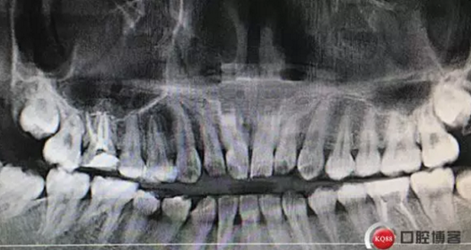

牙列完整,后牙中性關(guān)系,前牙開合,中線對齊。16合面大面積齲壞,內(nèi)褐色腐質(zhì),冷診無反應(yīng),叩痛(+-)。36合面樹脂充填,充填物在位,頰側(cè)冠折,折線位于齦緣下,冷診無反應(yīng),叩痛(+)。其他無殊。

治療計劃:36局麻下拔除碎片,攝片檢查余留牙體組織。16完善根管治療,擇期修復(fù)。

這是折線的位置,右是拔出的牙齒碎片。很明顯折裂波及遠中頰根。

兩周后復(fù)診,完善根管治療,牙齦恢復(fù)良好,牙周探診深度最大2mm,未探及根分叉。

根管治療完成攝片

治療完成,聚羧酸鋅水門汀暫封觀察一周,后期常規(guī)根管樁全冠修復(fù)。同期16治療完成。